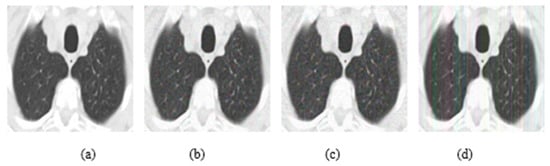

In addition, experiments were performed with FGSM, PGD, and Square Attack for ϵ values equal to 0.01, 0.03, 0.05, 0.07, 0.09, 0.12, and 0.15. In Figure 6, MRI with aforementioned attacks and ϵ = 0.01 are presented. The human eye cannot understand any difference between these images. In Figure 7, attacks with ϵ = 0.07 are depicted. Square Attack causes the biggest distortion compared to FGSM and PGD. However, small changes can be observed also in the other two attacks. In Figure 8, the ϵ value has been increased to 0.15, making the noise perceptible.

Figure 7.

(a) Initial Image, (b) FGSM attack with ϵ = 0.07, (c) PGD attack with ϵ = 0.07, (d) Square Attack with ϵ = 0.07.